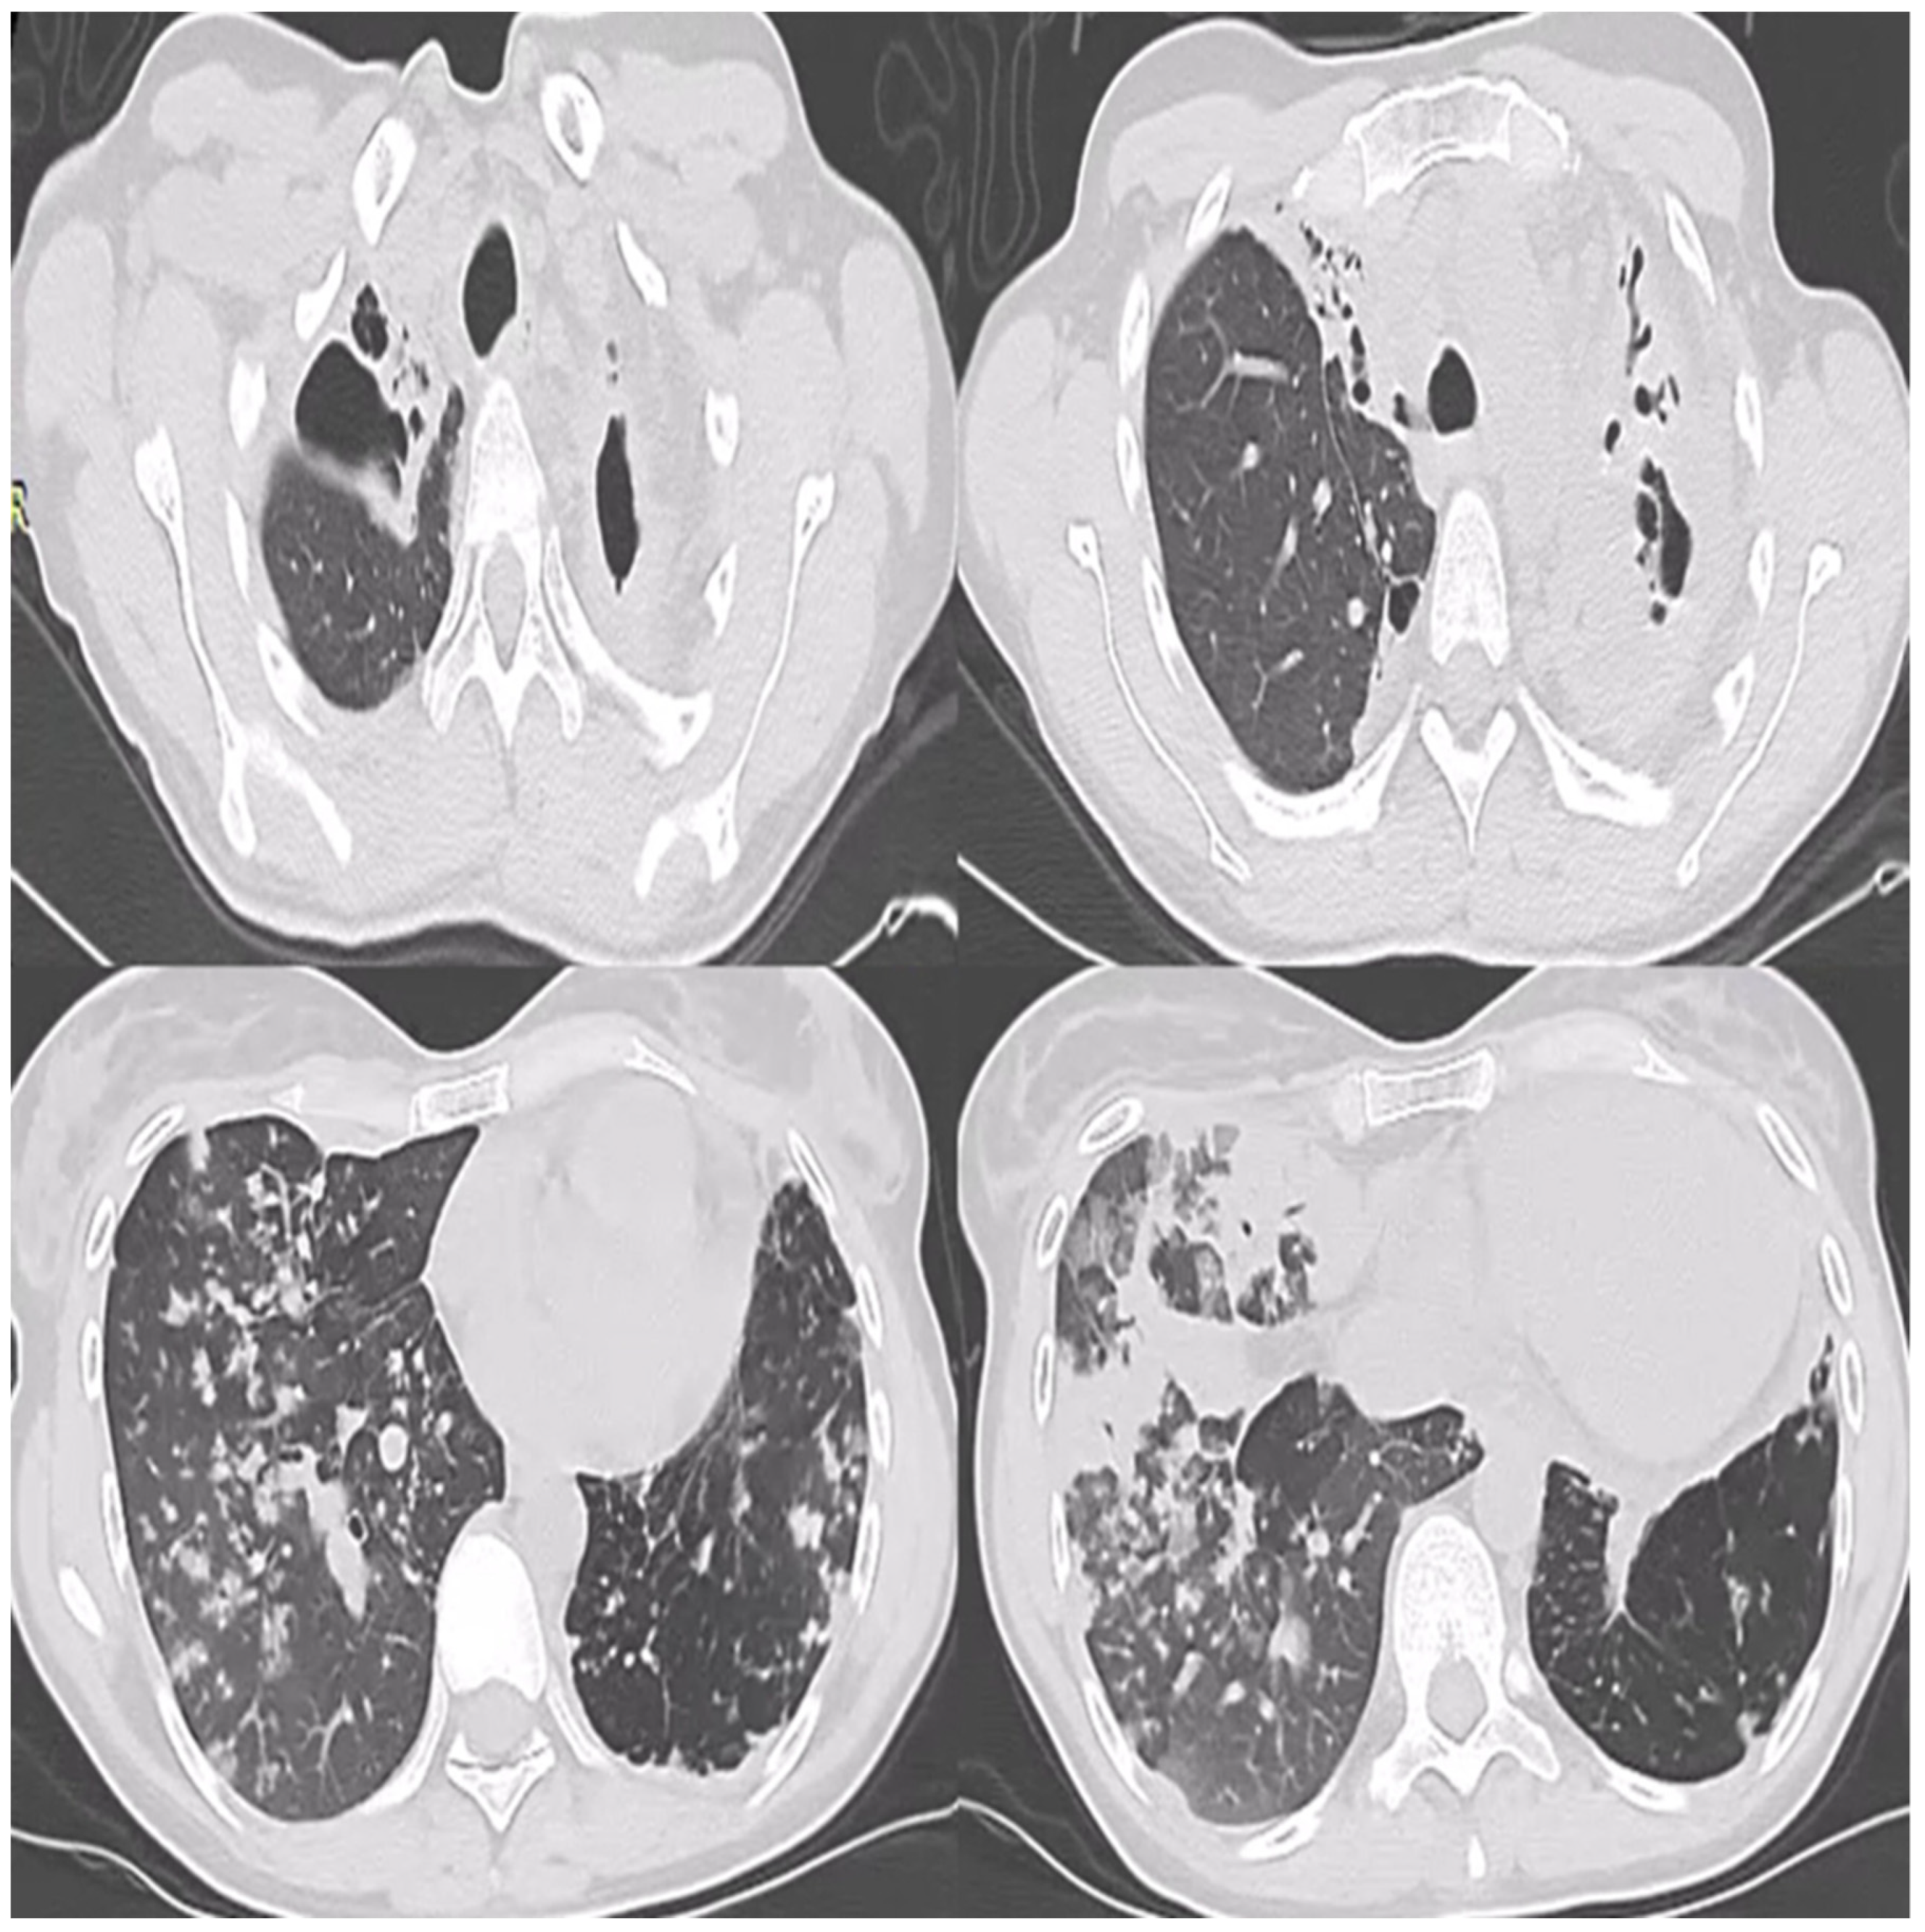

2. Case Report